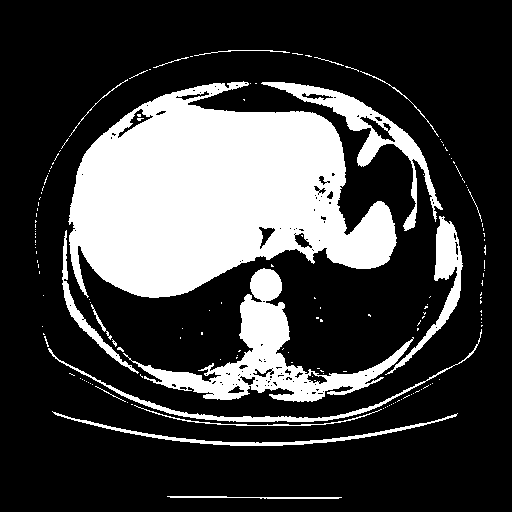

Reconstructed NATIVE CT scan (cycle consistency)

Full window (WL 1023.5, WW 4095 β†’ Low βˆ’1024, High +3071)

Actual HU range: [-1024.0, 3071.0]